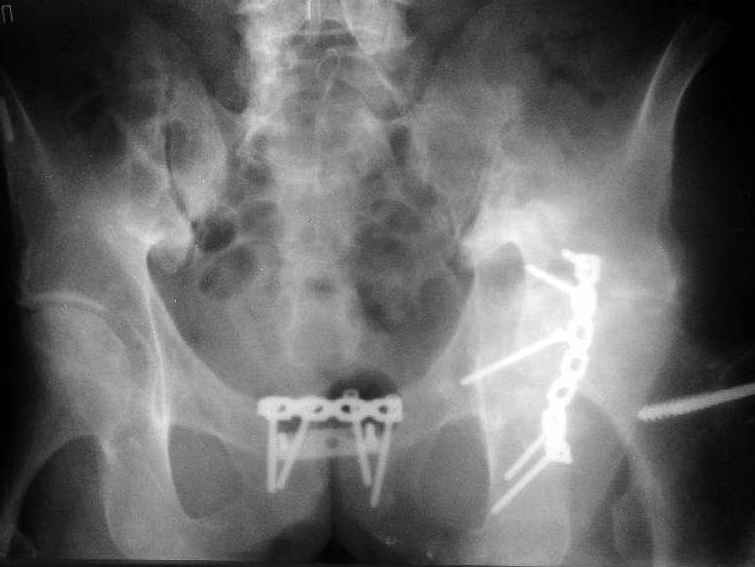

Пациент 53 лет травма 25.11.02. в салоне автомашины, получил множественные переломы ребер с ушибом легких и гемопневмотораксом, ротационно нестабильное повреждение таза: перелом боковых масс крестца, разрыв лонного сочленения, оскольчатый поперечный юкстатектальный перелом левой вертлужной впадины с центральным вывихом бедра и сегментарным переломом головки, перелом крыла правой подвздошной кости. Открытый многооскольчатый перелом костей правого предплечья, перелом правого бедра в нижней трети, перелом надколенника слева, перелом лодыжек левой голени с переломом заднего края левой большеберцовой кости подвывмхом стопы.Бедро срослось на вытяжении, лодыжки в гипсе, предплечье в аппарате. Под наше наблюдение попал 25.03.03. Выполнен чрескостный остеосинтез таза, с постепенной коррекцией положения отломков, затем 28.04.03 реконструкция вертлужной впадины для эндопротеза, синтез лонного сочленения. В настоящее время ходит с костылями, беспокоят боли в левом тазобедренном суставе, прогрессирует деформация головки. То есть в ближайших планах - эндопротезирование этого сустава. Однако смущает ряд моментов: В частности, на стороне предполагаемого эндопротезирования (левой) имеется разрыв собственной связки ниже надколенника, который подпаян к бедру (видно на фото сидя), то есть активного разгибания голени нет. А на правой стороне имеется штыкообразная деформация бедра, нет полного разгибания коленного сустава, хотя конечность опороспособна; ортопедическое укорочение 3 см.Вопросы: Что делать с левым надколенником и 4-главой мышцей? Восстанавливать ли ось и длину правого бедра? Если не трогать правое бедро, то на сколько компенсировать укорочение при эндопротезировании?

3. Left THA can be done, but I wouldn't try to shorten very much at THA site because he's already short due to protrusio (compare levels of lesser trochanters to your reference of choice on the pelvis) and any significant shortening at hip may lead to poor abductor tension and attendant risk of dislocation (offset stem and liner options may allow correction for these).